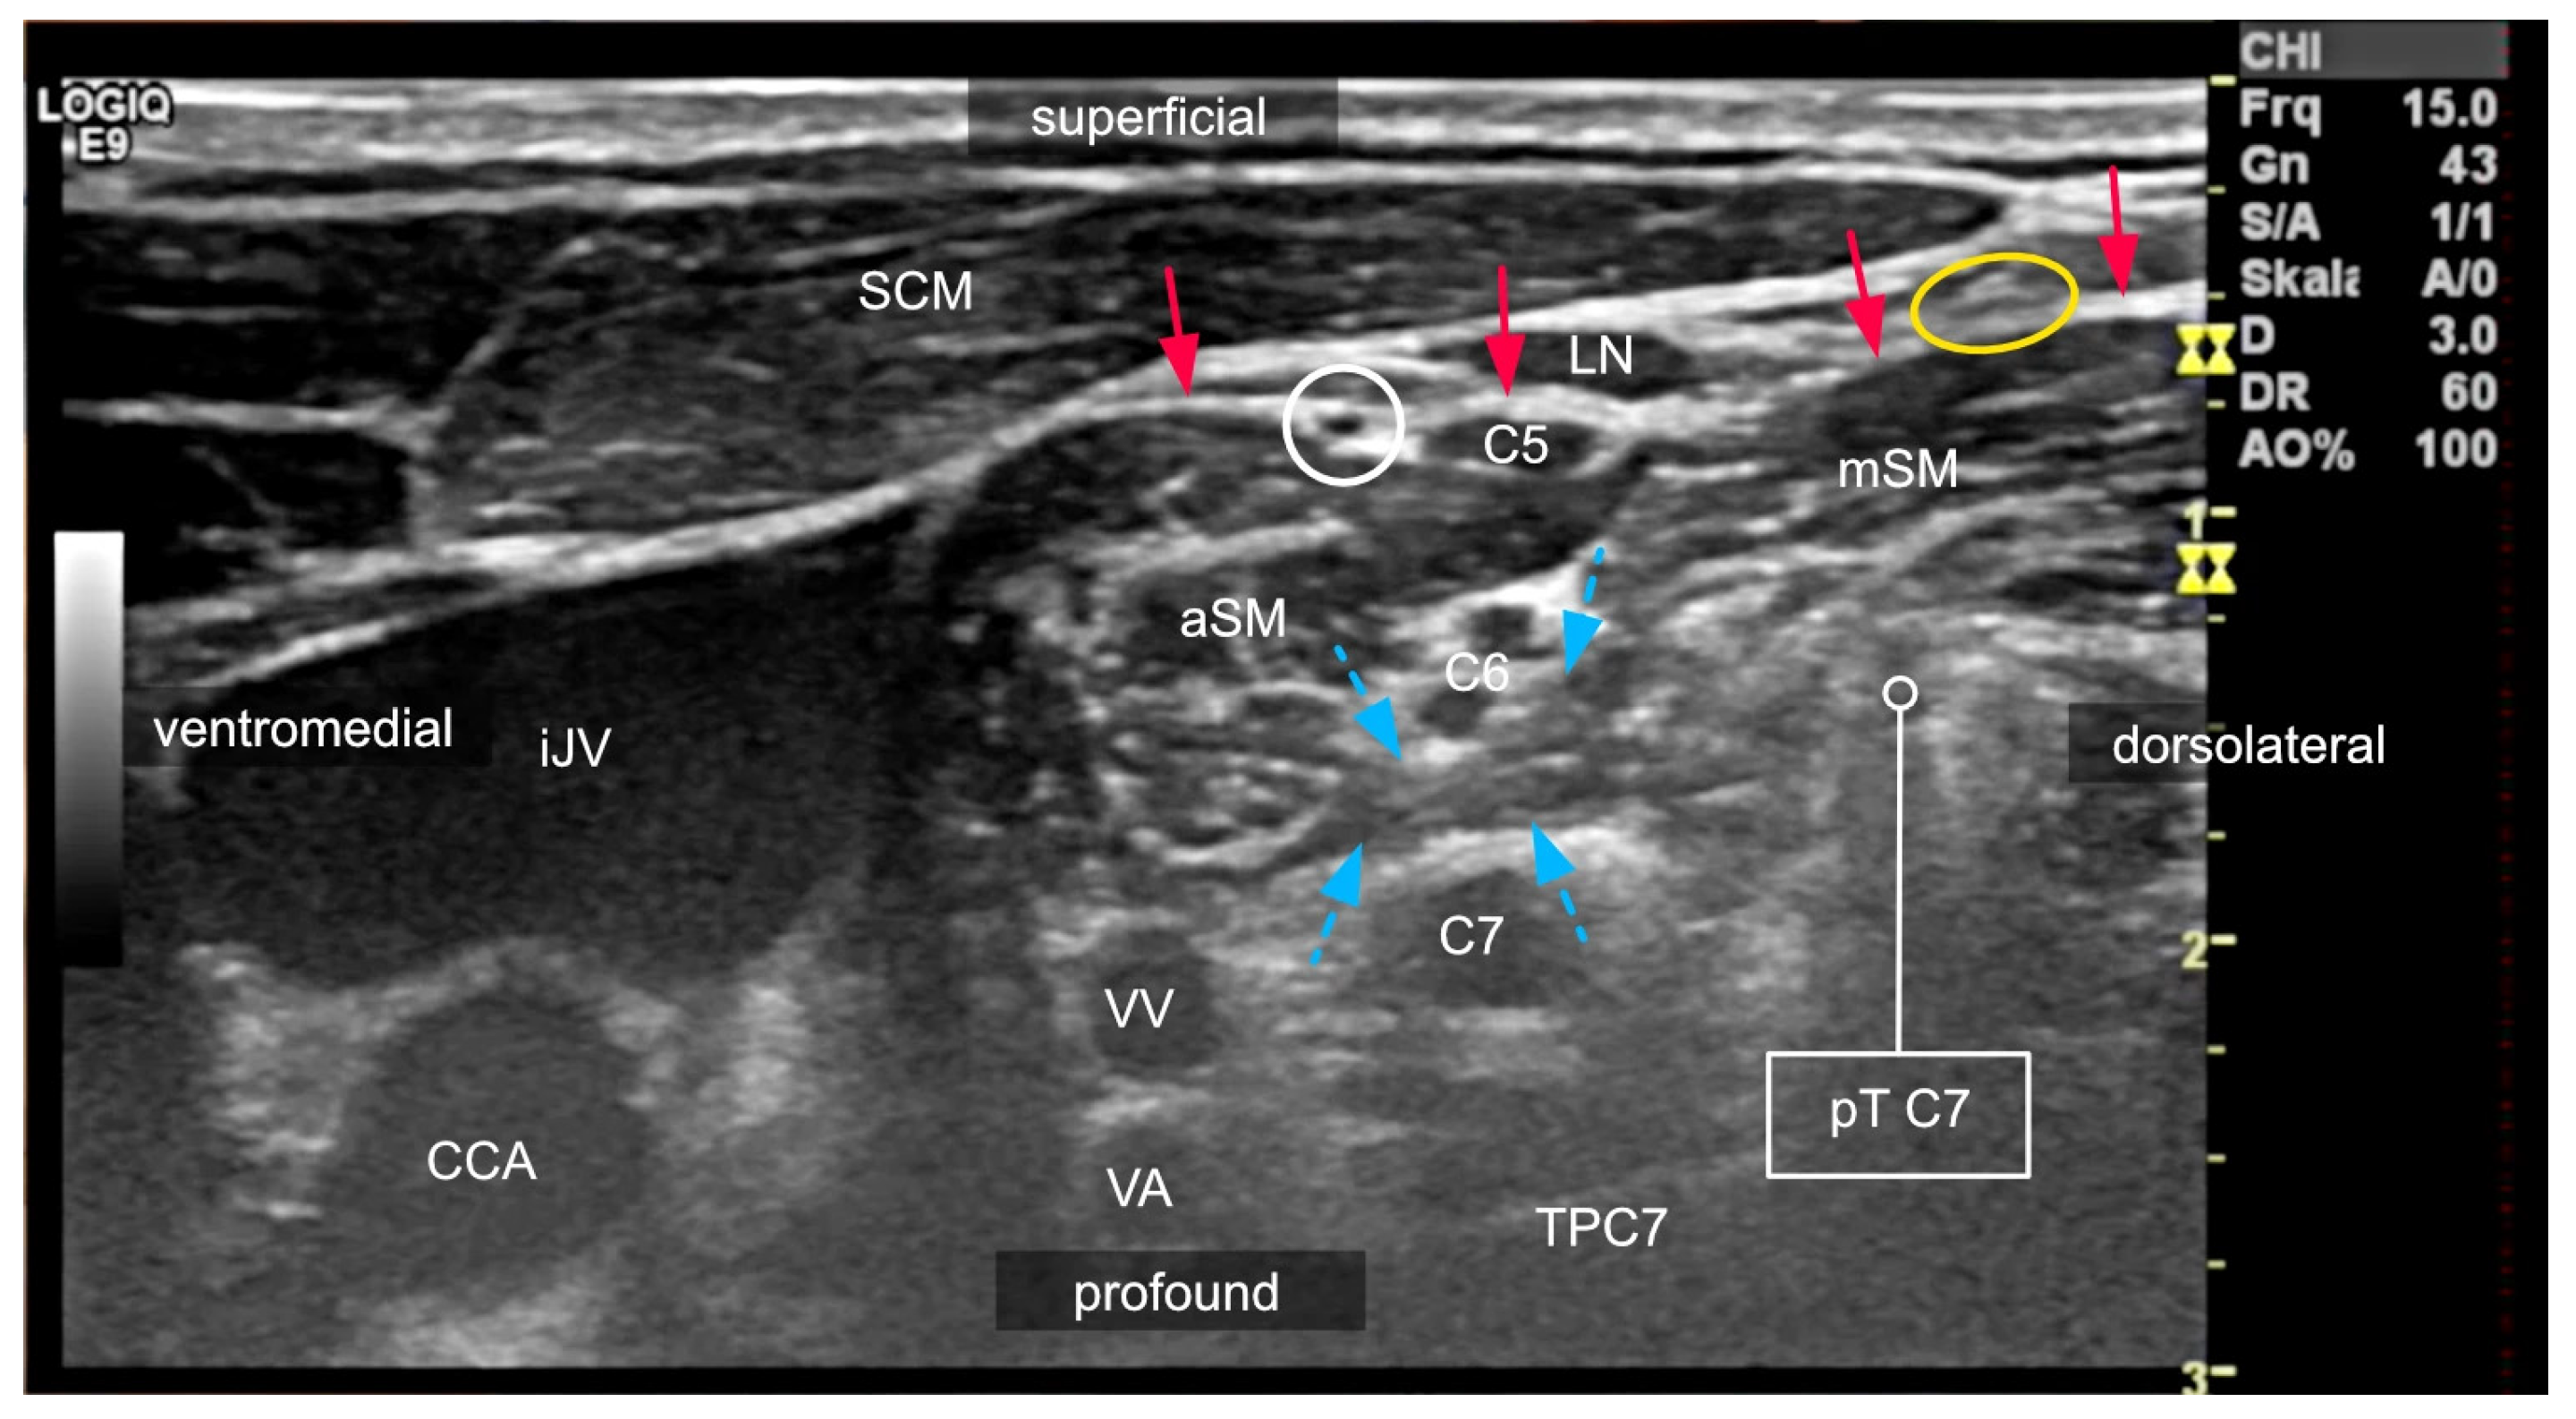

2. Relevant Anatomy for Interscalene Brachial Plexus Blocks

2.2. Anatomical Variations in the Scalene Gap

2.3. Variants of the Course of the Ventral Rami

2.4. Compartments of the Lateral Neck and Their Relevance to Side Effects

3.2. Interscalene Access

3.6. The Role of Ultrasound